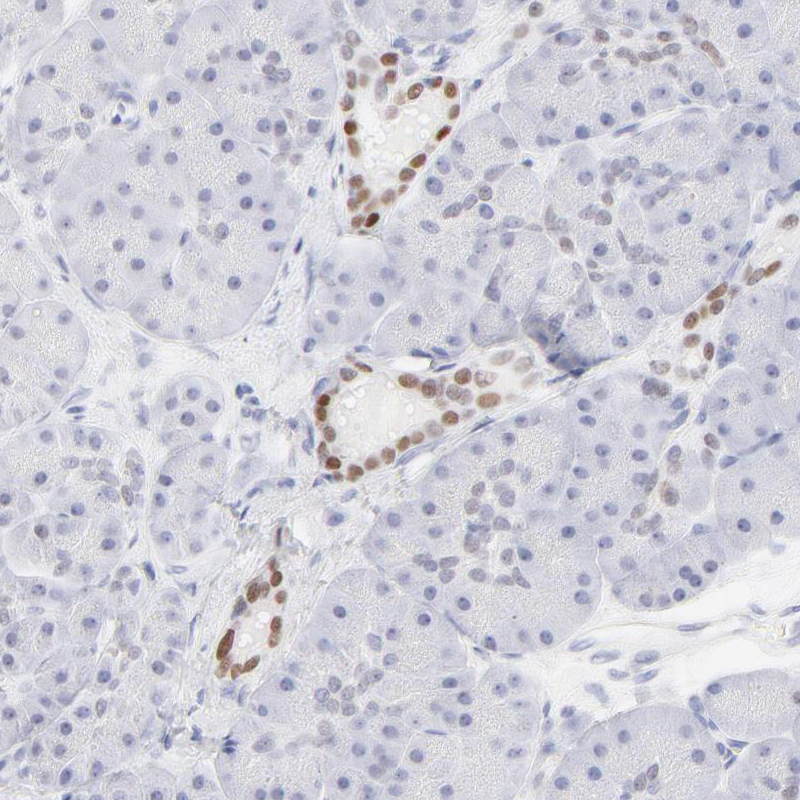

Immunohistochemistry analysis in human colon and skeletal muscle tissues using HPA003479 antibody. Corresponding ELF3 RNA-seq data are presented for the same tissues.